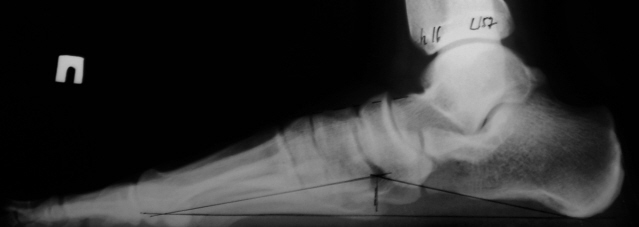

"У Вас когда-то находили плоскостопие? Нет никакого плоскостопия! "Здоров", "годен".

Рентгенография стоп:

ИзображениеИзображение